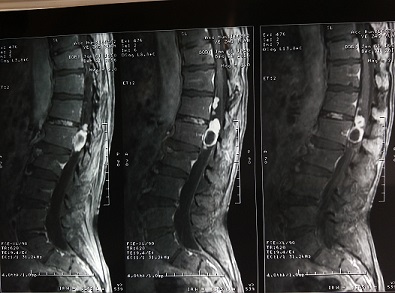

患者叶XX59岁男性,腰背部疼痛伴右侧腹股沟及臀部、大腿外侧放射痛3月余。半月前乘坐三轮摩托车后明显感觉疼痛加重,右下肢力量减弱,走路不稳,只能一直卧病在床。随后患者来我院检查。经我院骨科主治医师吴晓鸿的门诊细致检查,发现患者腰背部疼痛伴右下肢肌力减弱,通过CT、核磁等进一步检查,发现患者腰1—腰2椎管内巨大、多发肿瘤占位病变。

20161228日,在西安交大二附院王栋教授指导、协助下,吴晓鸿主治医师与李建栋副主任医师、王礼副主任医师及第五勇刚主治医师一起,顺利为该患者完成经后路全椎板减压、椎管内肿瘤切除、后路植骨内固定治疗。手术过程非常顺利,术后次日患者即感觉右下肢大腿及腹股沟疼痛症状消失。术后拍片复查见内固定稳定。减压、植骨效果良好。经过外二科护理团队的精心护理,患者现正在顺利恢复中。